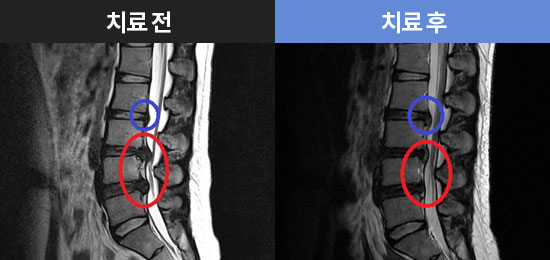

CHAMJALHAM MRI로 보는 치료결과

치료결과 더보기-